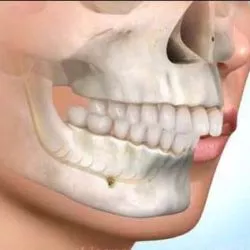

ישנם ליקויי סגר בהם הפער בין הלסתות (הן בגדול הלסת והן במיקום המרחבי שלה) הינו גדול מאד , ובהעדר גדילה של הלסתות (כלומר לאחר סיום תקופת הגדילה) לא ניתן לשנות את מקום הלסתות אלא באמצעות הזזתן בניתוח.

בטיפול המשלב בין יישור שיניים לניתוח בלסתות, יתכננו המומחה לכירורגית הפה והלסתות והאורתודונט את המיקום החדש של הלסתות הן מבחינה אסתטית והן מבחינה תפקודית, דבר שיאפשר מיקום נכון של השיניים במנשך תקין.

היתרונות בתהליך שכזה הם לא רק יצירת סגר תקין ואסתטי אלא גם שיפור ביכולת הבליעה והלעיסה, הדיבור והנשימה ולעיתים אף מערב תיקון של מבנה הסנטר והאף.